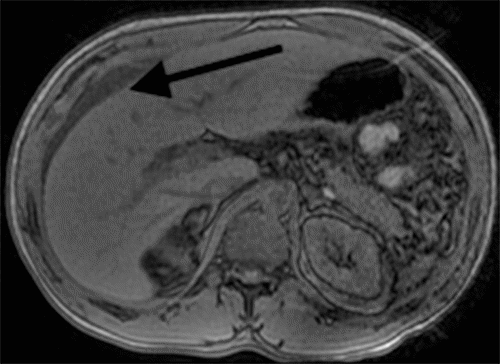

While the patient reported initial relief of symptoms within 48 hours of the initial procedure, he experienced a recurrence of nausea, distension, and abdominal pain. Post paracentesis, CT imaging of the abdomen pelvis failed to show extravasation of oral contrast from viscera (Figure 1) but revealed a contracted gallbladder and re-accumulation of ascites. A hepatobiliary iminodiacetic acid (HIDA) scan showed a biliary leak from the region of the gallbladder fossa (Figure 2). Magnetic resonance cholangiopancreatography showed recurrent ascites but no biliary obstruction (Figure 3). No traumatic injuries were identified on the initial imaging. Repeat paracentesis yielded one liter of bilious fluid, again with a resolution of symptoms.

Figure 1. CT Abdomen and Pelvis with Oral and Intravenous Contrast Showing Ascites and Contracted Gallbladder (arrows). Published with Permission